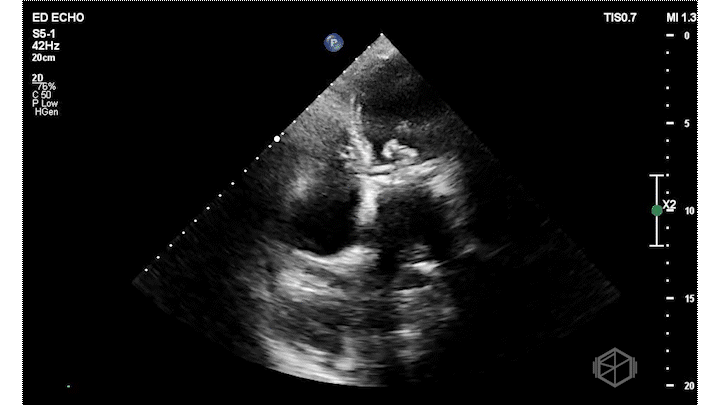

On this presentation Dr. Salman saw the following:

The ultrasound above shows an irregular appearing gestational sac with an irregular appearing structure intra-gestational sac without evidence of a heartbeat. Given this patient already had an US suggestive of pregnancy failure and she had heavy bleeding, this is indicative of pregnancy failure and inevitable vs. less likely incomplete abortion. She was taken to the OR for a D&C and discharged after the procedure without complications.

Diagnosis: Pregnancy failure with inevitable vs. incomplete abortion